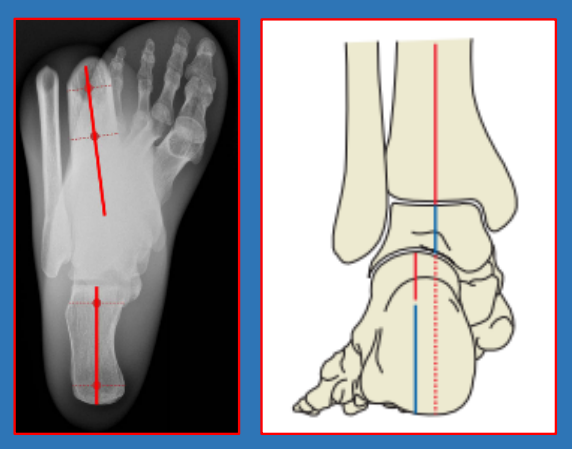

后足力线hindfoot alignment

长轴位long axial view,术中易获得。

后足力线位(改良Saltzman位)hindfoot alignment view,能更好暴露踝关节,术中难获得。

跟骨长轴的判断:Cobey法

正常后足力线:跟骨与胫骨干长轴平行,两轴线间垂直距离5-10mm,两轴夹角为跟骨内外翻角。